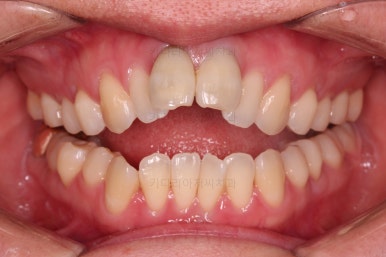

4. 마무리

앞니 임플란트의 색깔, 모양 등으로 몇 번의 수정 작업을 거친 뒤, 치료를 종료합니다.

잇몸뼈의 상태에 비해 매우 양호하게 임플란트가 완성되었고요.

개방교합, 2급 부정교합 등 모든 면에서 개선이 잘 되었습니다.

부산개방교합 전후 비교를 해보겠습니다.

웃을 때 잇몸선이 거의 보이지 않아 잇몸의 레벨이 위에 있었던 점이 완벽히 가려졌고요.

얼굴모습의 변화를 보면 거의 완벽하다 싶을 정도의 치료가 된 것이 아닌가 싶습니다.

앞니의 위치, 교합 개선, 웃는 모습 개선, 입매, 돌출감 개선, 옆선 등등 치료가 매우 고난도였던점을 생각한다면 이보다 더 좋은 교정 + 앞니 임플란트가 없다 싶을 정도의 치료였습니다.

임플란트 완료까지 총 3년 걸렸으며 앞니 제외 추가 발치는 없이 부산개방교합 교정하였습니다.